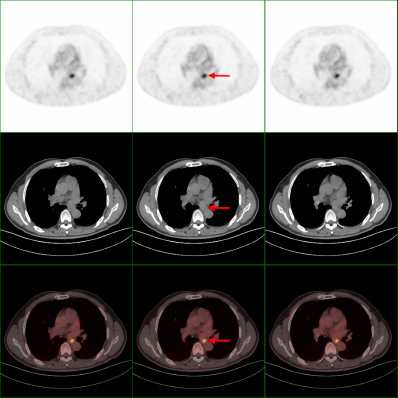

近期,在外务工的市民何先生无意间发现自己左颈部出现有肿块,随后去到当地医院检查,超声提示其左颈部有一个4.9厘米×2.9厘米的包块,彩超提示为:双侧颈部多发淋巴结。为得到进一步诊断和治疗,何先生选择回到了自贡,在市四医院进行PET/CT检查提示为食管癌伴颈部纵隔淋巴结转移。随后,医务人员为其进行胃镜下活检,明确为食管鳞癌。病情得以明确后,何先生在市四医院得到了妥善的治疗。